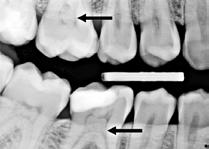

Fig. 11. A. Skematisk illustration af tand med pulpasten i pulpakammer og rodkanaler, hvilket kan gøre det vanskeligt at lokalisere kanalindgangene og udrense kanalerne (18). B. Bitewing-optagelse viser generaliseret dannelse af pulpasten i molarerne (pile). C. Periapikal optagelse af -6 med omfattende forkalkninger i pulpakammer og rodkanaler (pil).

Fig. 11. A. Schematic illustration showing tooth with pulp stone in the chamber and root canals creating potential difficulty in locating root canal orifices and instrumentation (18). B. Bitewing radiograph showing generalized pulp stone formation on molars (arrows). C. Periapical radiograph of mandibular left first molar with extensive calcifications in the pulp chamber and root canals (arrow).